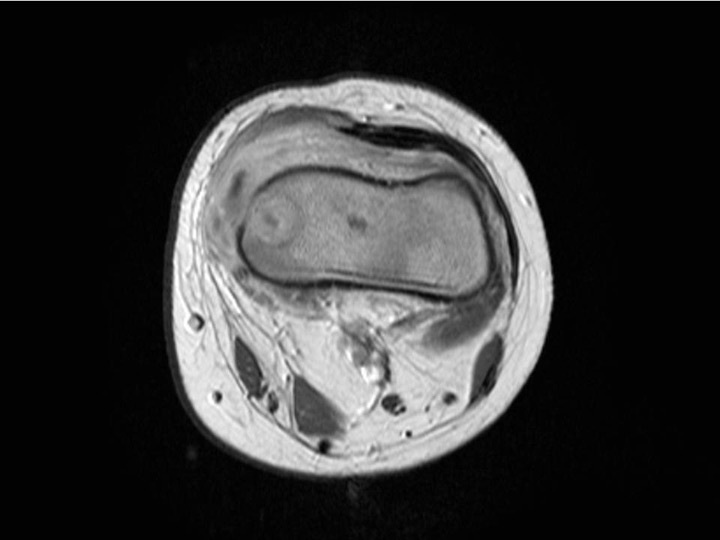

Figure 4

Sub-acute transphyseal osteomyelitis of the distal radius due to K. kingae in a 5-year-old boy who suffered from a chickenpox (varicella) infection three weeks before bone infection. This viral infection was considered as a predisposing factor for the development of osteomyelitis due to K. kingae resulting from a modulation of the immune system function.